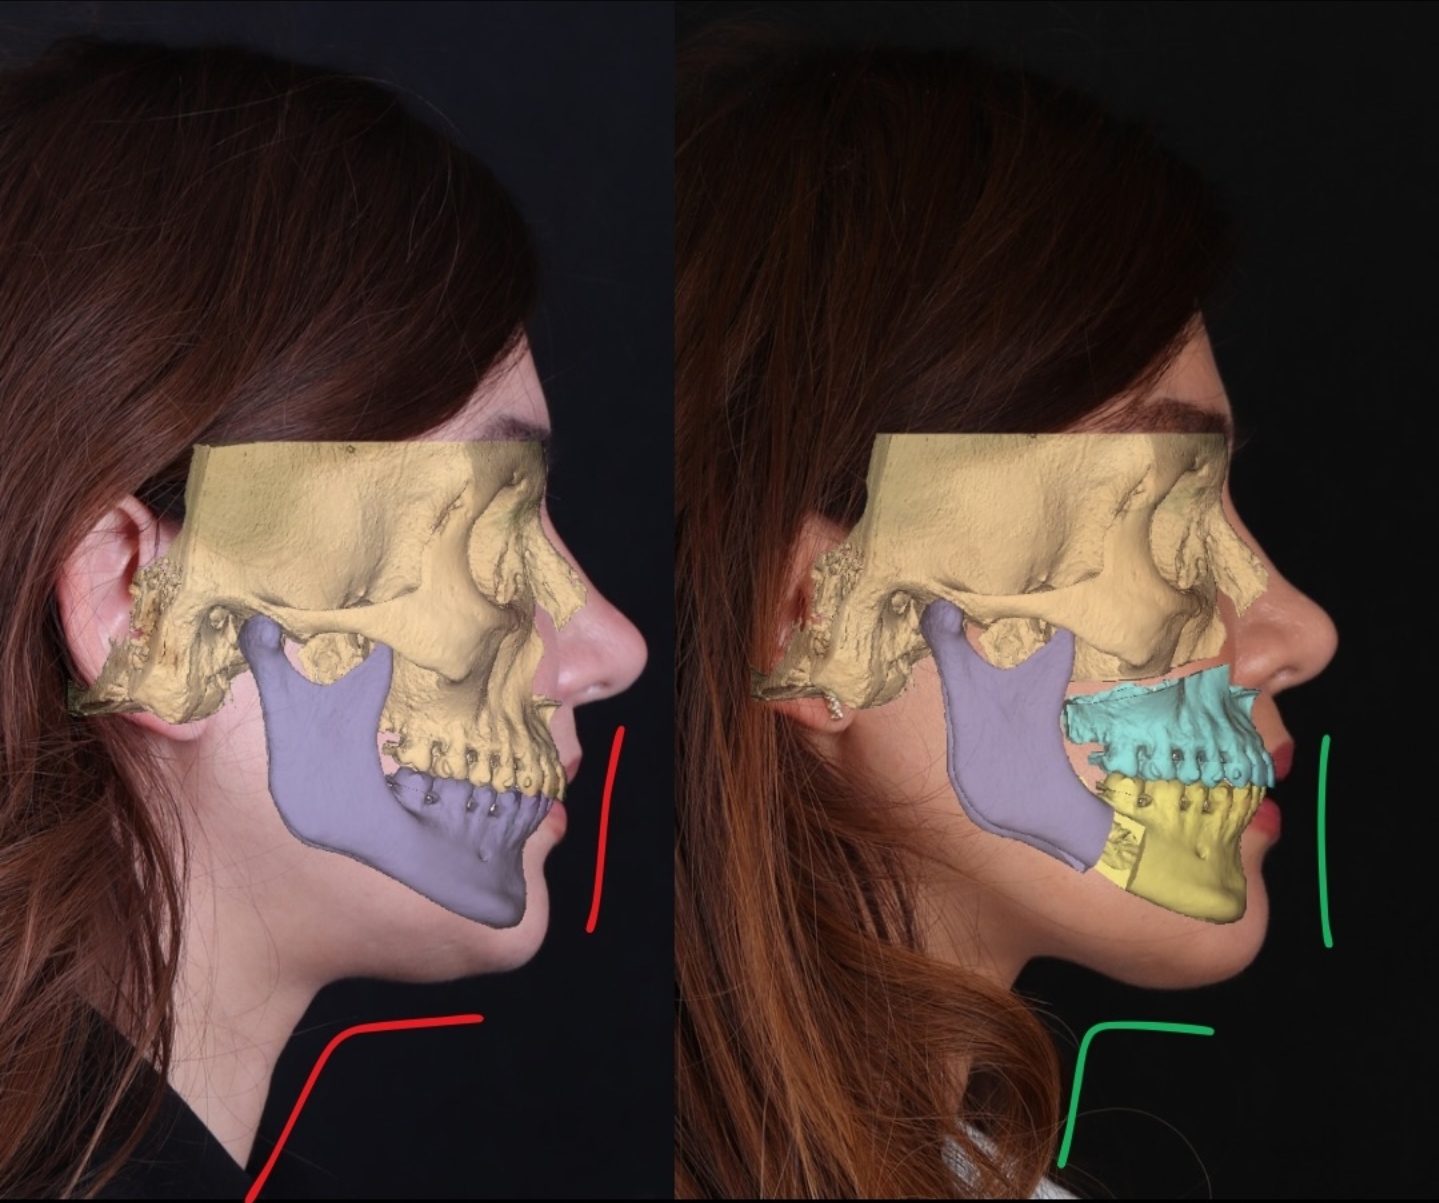

Case study #2)

A good way to check this is to see caucasoids who are class 3 - this eliminates and controls for the Asian trait of having an entirely recessed midface.

In the before the ANS is clearly further projected than the A point as can be seen by the curve. My logic follows that the nose is relatively projected which follows the norm of caucasoids but due to class 3 it is evident that the A point will be further back relative to the ANS. Now when he advanced the A point during the lefort 1 he fixed his profile - it looks nice and way better than the before but now the nasolabial curve has gone (not that it was good before but this is just theory talk).

Case study #2)

A good way to check this is to see caucasoids who are class 3 - this eliminates and controls for the Asian trait of having an entirely recessed midface.

In the before the ANS is clearly further projected than the A point as can be seen by the curve. My logic follows that the nose is relatively projected which follows the norm of caucasoids but due to class 3 it is evident that the A point will be further back relative to the ANS. Now when he advanced the A point during the lefort 1 he fixed his profile - it looks nice and way better than the before but now the nasolabial curve has gone (not that it was good before but this is just theory talk).